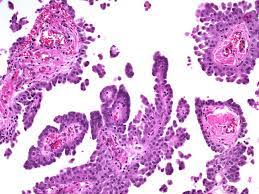

Malignant peritoneal mesothelioma (mpm) is an aggressive neoplasm that arises from the lining mesothelial cells of the peritoneum and spreads extensively within the confines of the abdominal cavity. Many of these signs and symptoms can be associated. Well differentiated papillary mesothelioma is characterized with a single layer of bland cuboidal cells lining fibrovascular cores, as demonstrated in this image. 13,28 malignant mesotheliomas of the peritoneum or pleura are rare tumors portending a poor prognosis. Home peritoneum peritoneum, omentum & mesentery mesothelioma. Additionally, omental mesothelioma is a rare type of mesothelioma that forms in the omentum, a part of the peritoneum that connects the stomach with other abdominal organs. Cystic epithelial neoplasms of the ovaries. A clinicopathologic study of 26 cases.

A clinicopathologic study of 26 cases. Cystic mesothelioma of the peritoneum. Well differentiated papillary mesothelioma is characterized with a single layer of bland cuboidal cells lining fibrovascular cores, as demonstrated in this image. , goldblum, j, hart wr. Mesothelioma of uncertain malignant potential. Peritoneal mesothelioma is the name given to the cancer that attacks the lining of the abdomen. The majority of previously reported cases developed in the peritoneum of young women without a history of asbestos exposure. 13,28 malignant mesotheliomas of the peritoneum or pleura are rare tumors portending a poor prognosis.

, goldblum, j, hart wr. Peritoneal mesothelioma is a cancer found in a thin membrane surrounding the abdomen known as the peritoneum. The american journal of surgical pathology. 13,28 malignant mesotheliomas of the peritoneum or pleura are rare tumors portending a poor prognosis. A clinicopathologic study of 22 cases. It is considered an indolent neoplasia, however only a minority of patients presents survival longer than ten years. Please type a message to the paper's authors to explain your need for the paper. Well differentiated papillary mesothelioma is characterized with a single layer of bland cuboidal cells lining fibrovascular cores, as demonstrated in this image. A clinicopathologic study of 26 cases. The peritoneum is the serous membrane forming the lining of the abdominal cavity or coelom in amniotes and some invertebrates, such as annelids. The majority of previously reported cases developed in the peritoneum of young women without a history of asbestos exposure. Additionally, omental mesothelioma is a rare type of mesothelioma that forms in the omentum, a part of the peritoneum that connects the stomach with other abdominal organs. Cystic mesothelioma of the peritoneum.